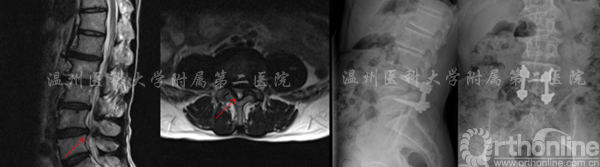

术前MRI提示:腰4/5管狭窄(左) 术后X线提示:固定良好(右)

左图:提示腰3/4椎管狭窄  右图:提示腰4/5椎管狭窄

术后X线显示CBT螺钉未松脱、断裂,螺钉位置良好